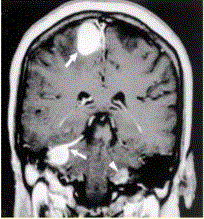

问题 患者男,20岁,头痛、步态不稳。MRI显示如下图。 关于神经纤维瘤病的影像学表现,正确的是

选项 A.Ⅰ型主要累及外周神经的丛状纤维瘤及视神经胶质瘤 B.Ⅱ型可见蝶骨大翼发育不良,眶上裂增宽等 C.皮肤caféanlait斑,腋窝、腹股沟雀斑常见于Ⅱ型 D.Ⅰ型常见多发脑神经鞘瘤、脑膜瘤及脊神经肿瘤 E.NF-2相关的神经鞘瘤较散发的增生活性高而且存在侵袭性

答案 A